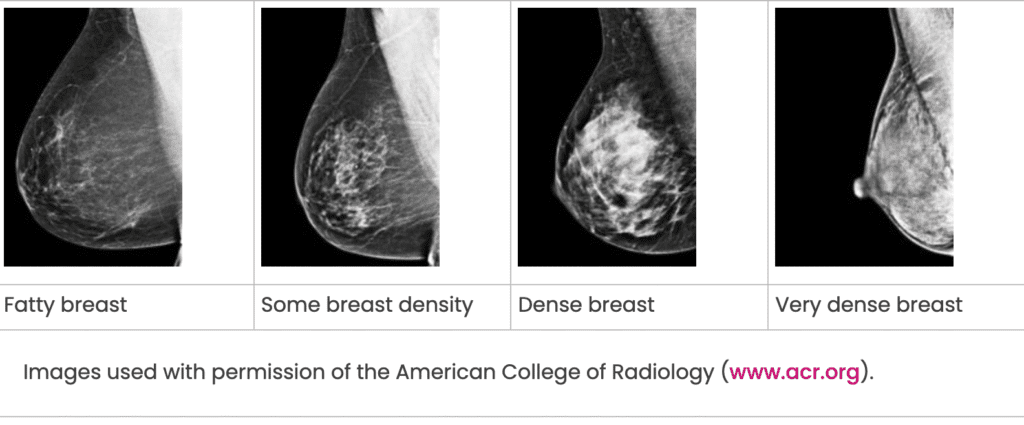

If a mammogram shows you have more tissue in your breast than fat, you have what’s called dense breasts. Having dense breasts does not describe how your breasts feel; instead, it describes mammogram findings.

The reports include an overall finding stating whether your breasts are dense or if they are not dense, as well as additional information and detail about the level of density:

- Breasts are almost entirely fatty (not dense).

- Breasts have scattered areas of fibroglandular density (not dense).

- Breasts are heterogeneously dense, which may obscure small masses (dense).

- Breasts are extremely dense, which lowers sensitivity of mammography (dense).